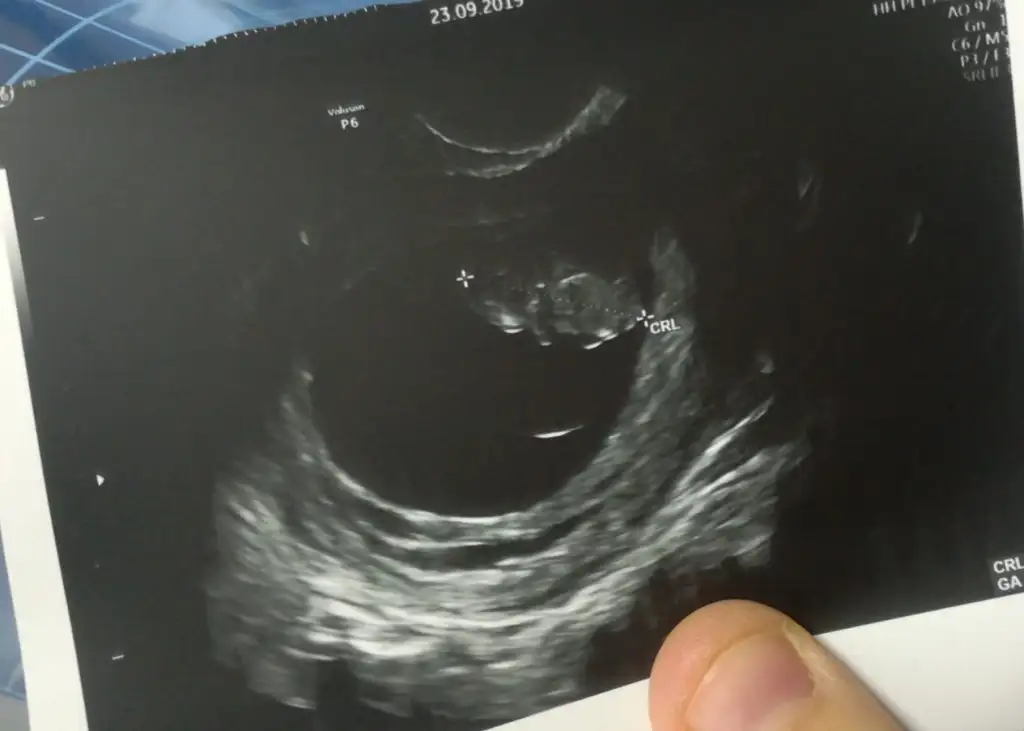

Buna göre kızEki Görüntüle 2309620 Bana da yorum yapar mısınız acabavajinal ultrason

Saga yakın kız vajinalsa erkek

Vajinalsa erkek karındansa kızcinsiyetimiz nedir teyzeleri

Tesekkur ederim bu karindan ultrason.Saga yakın kız vajinalsa erkek